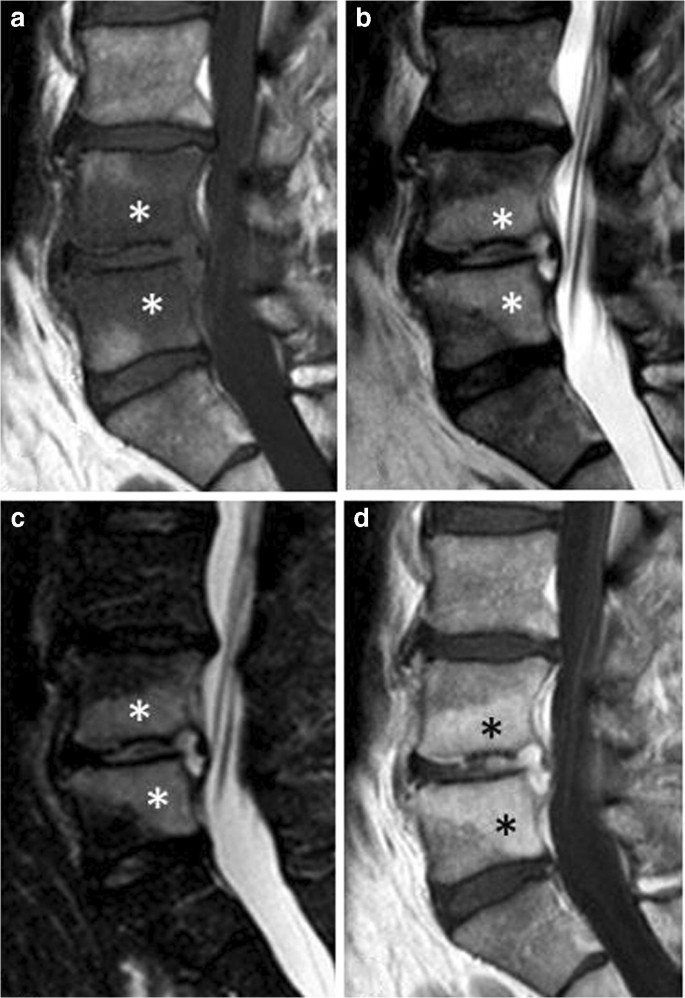

The information provided does not constitute a diagnosis. Bone marrow edema is simply a condition where fluid is found within the bone. Bone marrow edema arises from altered stresses on bones due to osteoarthritis, biomechanical abnormalities, coalitions, infection, and trauma.

The purpose of this pictorial essay is to provide guidelines based on clinical history and specific mri patterns and locations to accurately identify the cause of ankle bone marrow edema. The information provided does not constitute a diagnosis. Bone marrow edema is a condition when excess fluids in the bone marrow build up and cause swelling. It is often caused by a response to an bone marrow edemas may not bother you at all, or they may be painful and inconvenient.